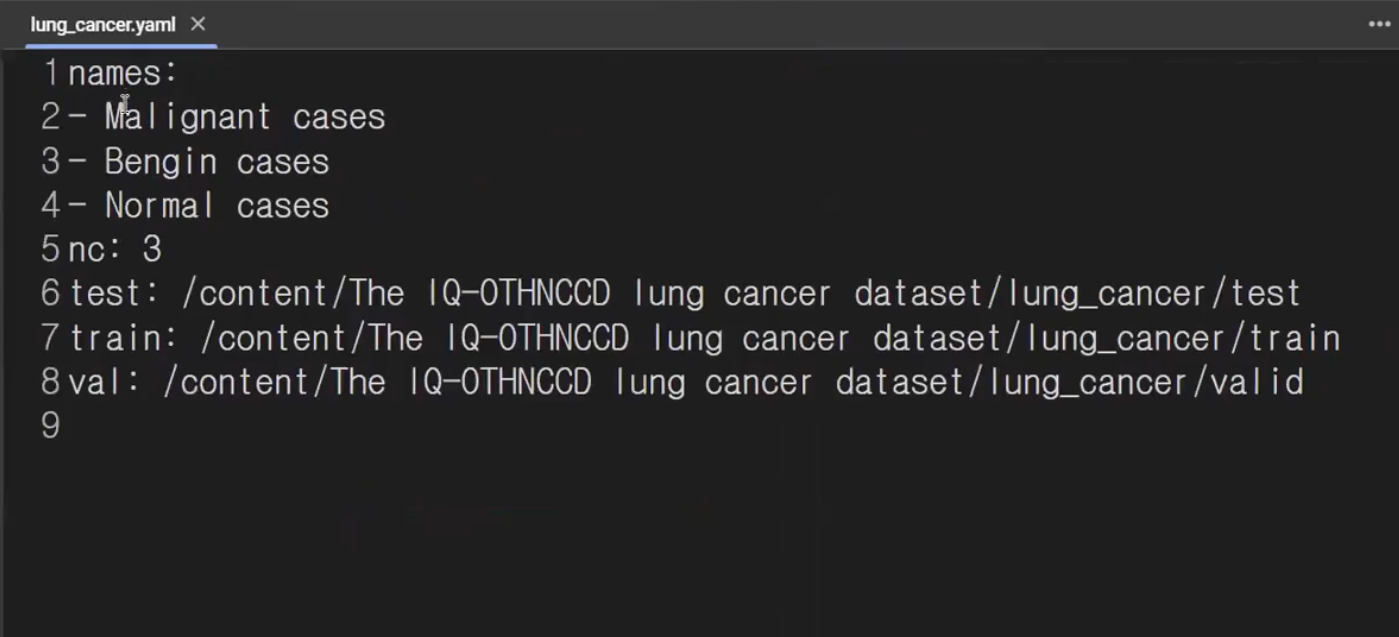

yaml 이란?

yolo에 집어넣을 경로, 설정을 저장하는 파일입니다.

data= dict()

data['train']= train_root

data['val']=valid_root

data['test']=test_root

data['nc']= len(cls_list) #3

data['names'] = cls_list

#이렇게 정리한 딕셔너리를 파일로 저장하기

with open(f'{project_root}/lung_cancer.yaml', 'w') as f:

yaml.dump(data, f)

nc는 class의 개수입니다 #3개가 될것임

저렇게 정리한 딕셔너리를 파일로 저장하면 yaml파일로 만들어집니다.